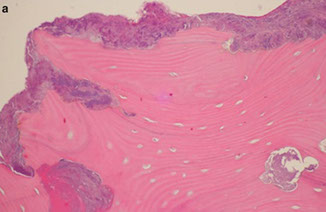

Keratocystic Odontogenic Tumor (KCOT)

- previously odontogenic keratocyst (OKC) but renamed 2/2 potential for aggressiveness, recurrence and genetic abnormalities

Parakeratin lined cyst-like tumor in bone (posterior mandible), ~1/10 of odontogenic cysts, MC up to 30 yo; 9/10 solitary

- multiple tumors assoc c Gorlin syndrome (nevoid basal cell carcinoma syndrome [NBCCS])

- may arise from dental lamina; usually cause jaw swelling

- grossly has thin wall c unerupted tooth

Micro: uniform epithelium of palisading hyperchromatic basal cell cuboidal to columnar cells w/o rete ridges

- luminal side c wavy "corrugated" parakeratotic epithelial cells and can have keratotic debris inside

Genes: 2-hit mech in bi-allelic loff of PTCH ("patched") tumor suppressor on 9q22.3 causing dysregulatio nof p53 and cyclin D1 oncoproteins

Tx: decompression , enucleation, excision (may be excessive)

Px: up to 1/2 recur (possibly 2/2 daughter cysts in the wall that are not excised, or fragmentation of the cyst wall during excision)